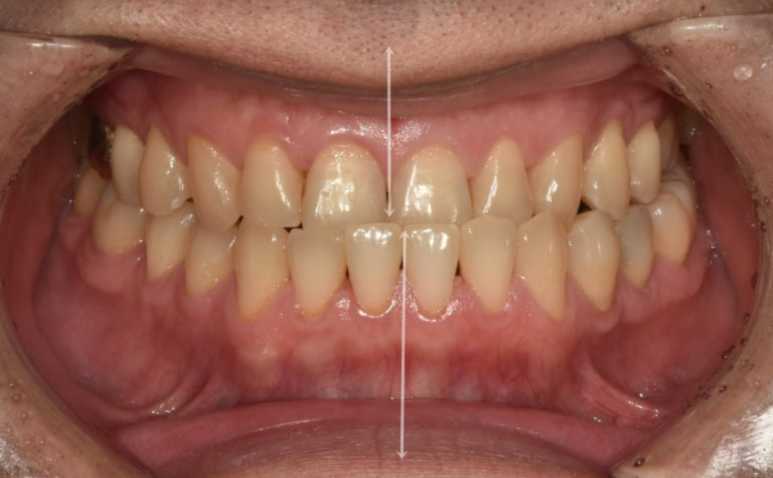

치열은 가지런한 편이나 앞니 반대교합으로 오랫동안 지내오면서 아래앞니에 부딫쳐 위 앞니 마모도가 심합니다.

인비절라인으로 비발치 교정 권유드렸습니다. 아래 전체치열을 사랑니 공간으로 밀어내어 앞니 반대교합과 중심선 불일치는 해결하기로 하고요

앞니 반대교합은 해결 되었으나 여전히 중심선이 미세하게 안 맞고

중심선은 잘 맞아졌습니다.